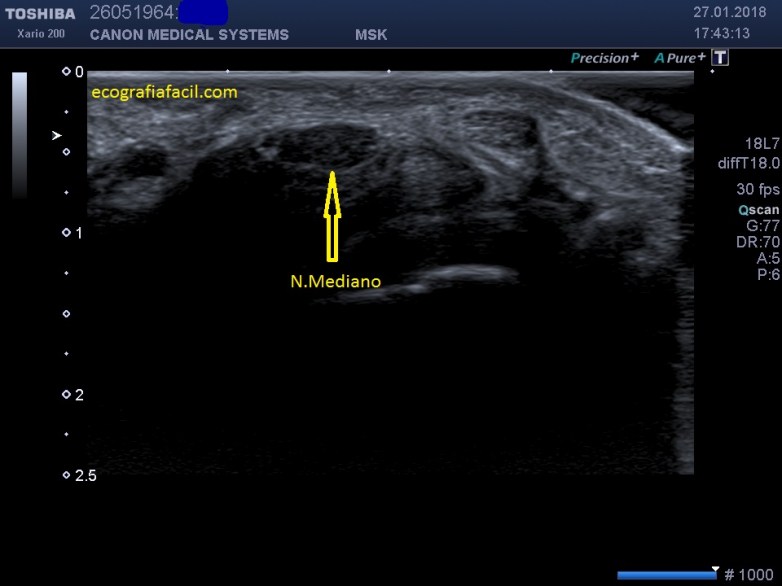

Síndrome del Túnel del Carpo:

Síndrome compresivo por excelencia de la extremidad superior  a su paso por el túnel carpiano.

Ecograficamente:

Síndrome del Túnel del Carpo incipiente: No hay cambios ecográficos o cambios inespecíficos.

Síndrome del Túnel del Carpo crónico: Cambios aspecto ecográfico del Nervio típicos de neuropatía, engrosamiento del grosor del Nervio con hipoecogenicidad, como puedes ver en estas preciosas imágenes de un N.Mediano engrosado e hipoecogénico en el Túnel del Carpo, cedidas amablemente por Don Javier Álvarez González, Profesor de Fisioterapia Responsable de Imagen Médica de la Universidad Francisco de Vitoria, excelente profesional, pero sobre todo, un amigo…Gracias Profesor¡¡¡